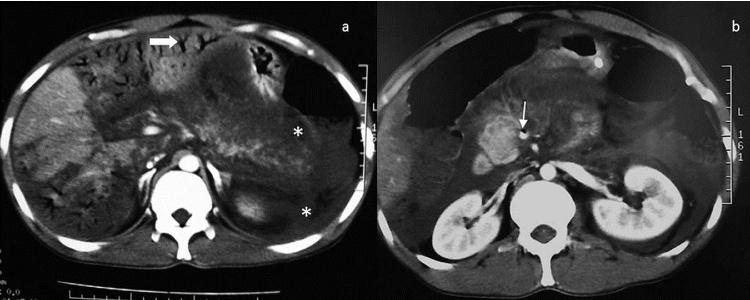

Etiologies were mesenteric infarction (n=5), sigmoid diverticulitis (n= 1), septic shock (n=1), postoperative peritonitis (n=1), acute pancreatitis (n=1), iatrogenic cause (n=3) and idiopathic after a laparotomy (n=1). The outcome was fatal in for 6 patients. Abundance of HPV was expressed in total number of hepatic segments involved. The involvement of 3 or more segments was a sensitive sign for lethal outcome with high sensitivity (100%) but it was not specific (50%). Negative predictive value of this sign was 100% (p≤0.005). Positive predictive value of PI for death was 100% (p≤0.001).

Abundance of HPVG is correlated with prognosis. The presence of PI announces poor outcome Negative predictive value of presence of HPVG in 3 or more segments is interesting. Predicting prognosis with CT can help surgeons to assess the most adequate treatment. Iatrogenic causes are increasingly described after interventional radiology procedures with favorable course.

The first etiology radiologists should look for in front of HPVG involving more than 3 hepatic segments and associated with PI is intestinal necrosis which announces a poor prognosis. This study shows that outside of shock situations, HPVG involving 2 or less hepatic segments without PI predicts a good outcome.

病因包括肠系膜梗死(n = 5)、乙状结肠憩室炎(n = 1)、感染性休克(n = 1)、术后腹膜炎(n = 1)、急性胰腺炎(n = 1)、医源性原因(n = 3)和剖腹术后特发性(n = 1)。6例患者预后为致命。HPV的丰度以受累肝段总数表示。3个或更多肝段受累是致命结局的敏感征象,敏感性高(100%)但不具有特异性(50%)。该征象的阴性预测值为100%(p≤0.005)。PI对死亡的阳性预测值为100%(p≤0.001)。

讨论

对于累及3个以上肝段且伴有PI的HPVG,放射科医生首先应寻找的病因是肠坏死,这预示着预后不良。本研究表明,在非休克情况下,累及2个或更少肝段且无PI的HPVG预示预后良好。